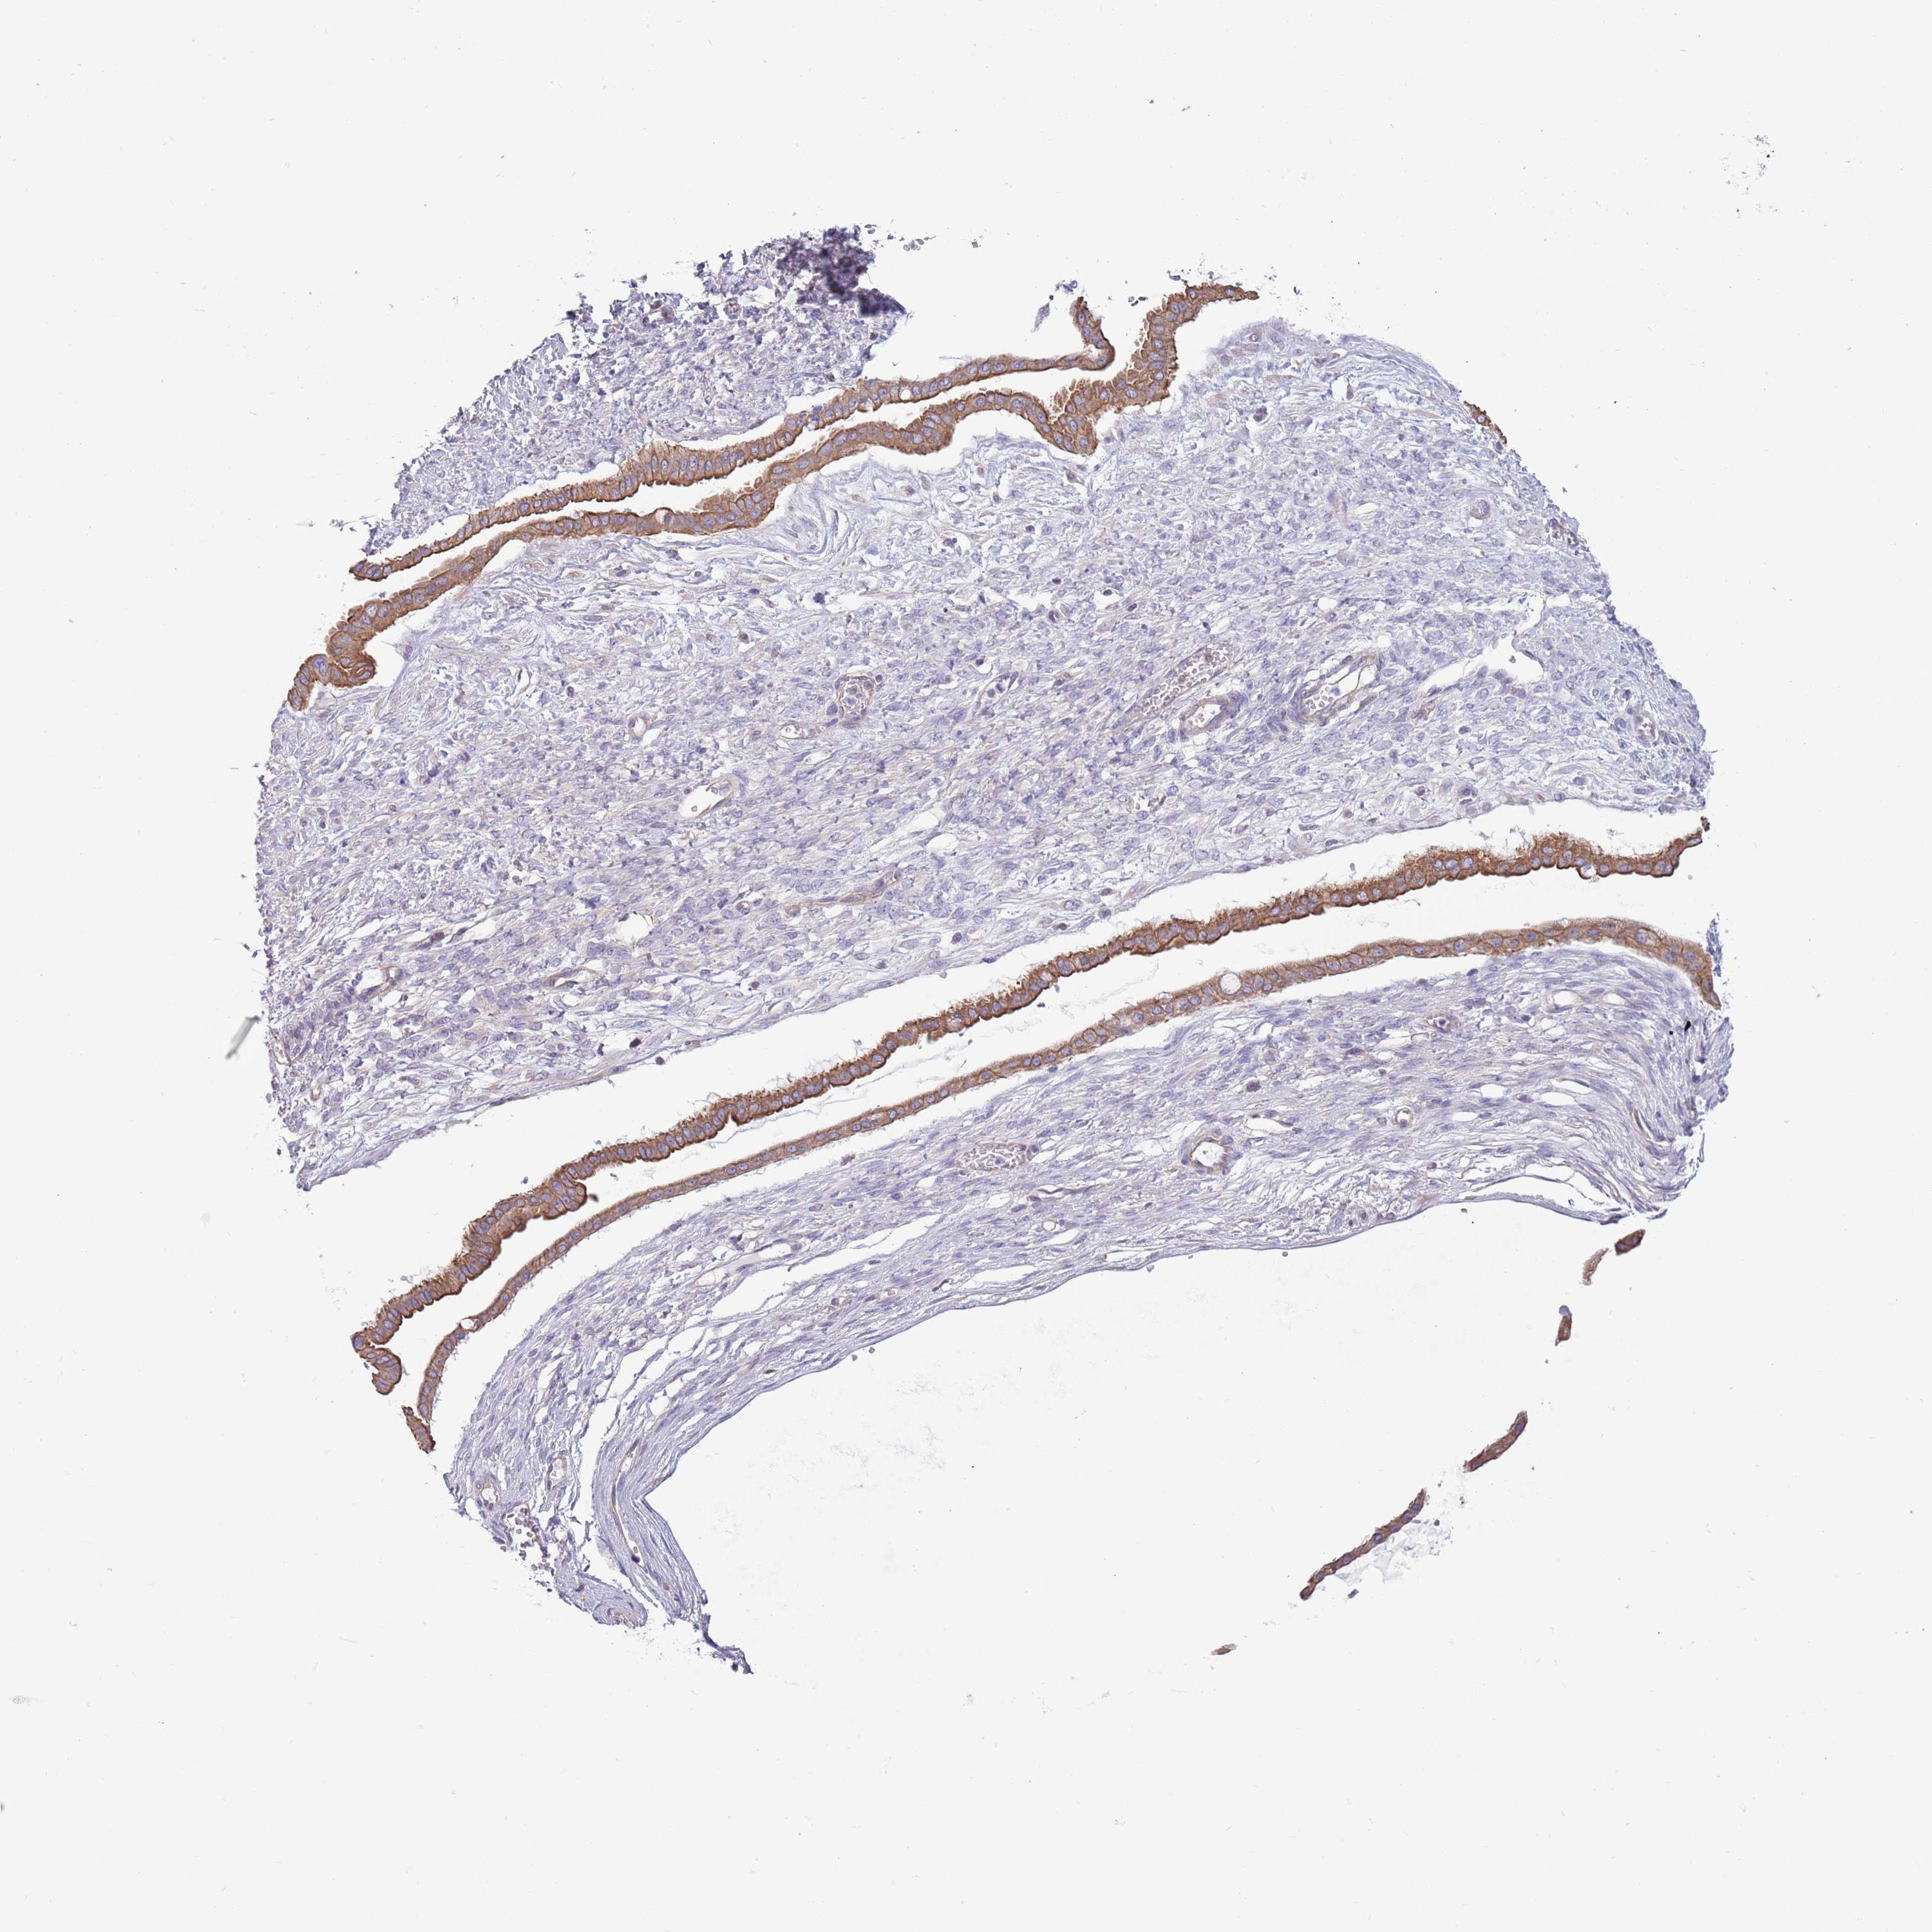

OVARIAN CANCER - Protein expressioni

A mouse-over function shows sample information and annotation data. Click on an image to view it in a full screen mode. Samples can be filtered based on level of antibody staining by selecting one or several of the following categories: high, medium, low and not detected. The assay and annotation is described here.

Note that samples used for immunohistochemistry by the Human Protein Atlas do not correspond to samples in the TCGA dataset.

Antibody stainingi

Antibody staining in the annotated cell types in the current human tissue is reported as not detected, low, medium, or high, based on conventional immunohistochemistry profiling in selected tissues. This score is based on the combination of the staining intensity and fraction of stained cells.

Each image is clickable and will lead to virtual microscopy that enables deeper exploration of all samples and also displays staining intensity scores, fraction scores and subcellular localization as well as patient and tissue information for each sample.

Antibody HPA041301

Antibody HPA044239

Staining

High

Medium

Low

Not detected

Intensity

Strong

Moderate

Weak

Negative

Quantity

>75%

75%-25%

<25%

None

Location

Nuclear

Cytoplasmic/membranous

Cytoplasmic/membranous,nuclear

Cystadenocarcinoma, serous, NOS

Carcinoma, endometroid

Cystadenocarcinoma, mucinous, NOS

Carcinoma, NOS